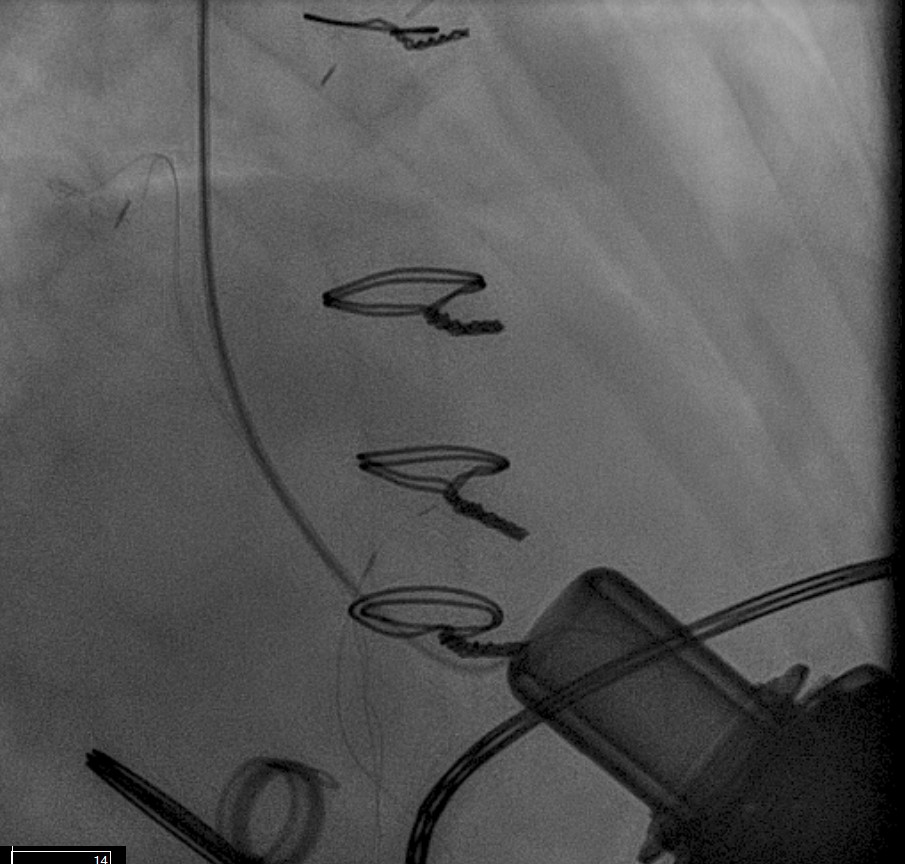

LVAD deactivation can be achieved by surgical explant via median sternotomy or via a hybrid surgical/percutaneous approach described as decommissioning [37]. Complete explant is recommended in younger patients and those with infected drivelines and/or pump. Decommissioning implies retention of the pump within the body. The driveline is cut and buried subcutaneously. The outflow cannula must be occluded to prevent closed loop regurgitant flow from the aorta into the left ventricle, typically with endovascular occlusive device/s at the OFG-ascending aorta anastomosis (Fig. 12). Surgical decommissioning can be achieved minimally invasively and without cardiopulmonary bypass.

Fig. 12. LVAD decommissioning. Outflow cannula occlusion with a series of three large Amplatzer vascular plug 2 (AVP2) from the proximal end to the distal end of the cannula.